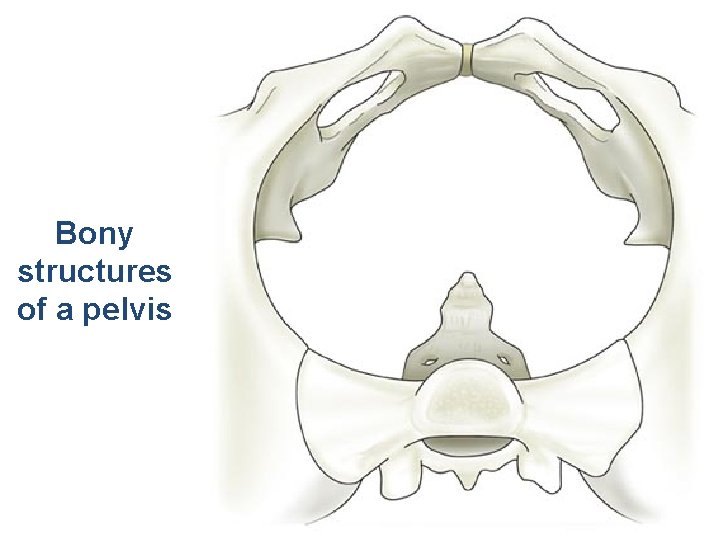

Elements comprising the Pelvis • Bones – Ilium, ischium and pubis fusion • Ligaments • Muscles – Obturator internis muscle – Arcus tendineus levator ani or white line – Levator ani muscles – Urethral and anal sphincter muscles

Bony pelvis • Composition: formed by paired hip bones, sacrum, coccyx, and their articulations • Two portions – Greater pelvis – Lesser pelvis • Terminal line ( pelvic inlet): formed by promontory of sacrum, arcuate line, pectin of pubis, pubic tubercle, upper border of pubic symphysis • Pelvic outlet: formed by tip of coccyx, sacrotuberous ligament, ischial tuberosity, ramus of ischium, inferior ramus of pubic symphysis

Anatomy: Bones of Pelvis • • • Sacrum Coccyx Innominates (2) Ilium Ischium Pubis

Bony structures of a pelvis